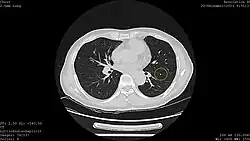

Calcified lung nodule seen on Low Dose Chest CT (circled)

Calcified lung nodule seen on Standard Dose Chest CT (circled)